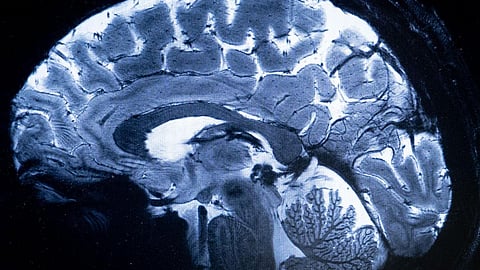

கேரள மாநிலத்தில் அமீபா நுண்ணுயிரியால் ஏற்படும் மூளையழற்சி பாதிப்பு வேகமாக பரவி வருகிறது. இதுவரை அந்நோய் பாதிப்புக்கு மூன்று பேர் உயிரிழந்துள்ளனர். அசுத்தமான தண்ணீரில் உள்ள அமீபா மூலம் உருவாகும் என்சபலிட்டிஸ் எனப்படும் மூளையழற்சி பாதிப்பு ஏற்படுகிறது. சுகாதாரமற்ற தண்ணீரில் குளிக்கும்போது சுவாசப் பாதைவழியே ஊடுருவிச் செல்லும் அந்த வகை அமீபா, நேரடியாக மூளையில் வீக்கத்தை ஏற்படுத்துகிறது. காய்ச்சல், வாந்தி, மயக்கம்,தலைவலி, மனக் குழப்பம், பிதற்றல், வலிப்பு போன்றவை முக்கிய அறிகுறிகள் ஆகும். பாதிக்கப்பட்டவர்களுக்கு உடனடியாக தீவிர சிகிச்சை அளிக்காவிட்டால் உயிரிழப்பை ஏற்படுத்தும் அபாயம் உள்ளது.